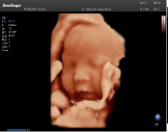

4容積探頭

積探頭是在二維圖像的基礎(chǔ)上,將連續(xù)采集的空間分布位置,經(jīng)過計算機重建算法,從而獲得完整的空間形態(tài)。

適用于:胎兒面部、脊柱和肢體等。

優(yōu)勢特點:快速獲取、掃查連續(xù)均勻、解剖結(jié)構(gòu)顯示為容積數(shù)據(jù)、準(zhǔn)確進行容積測量。